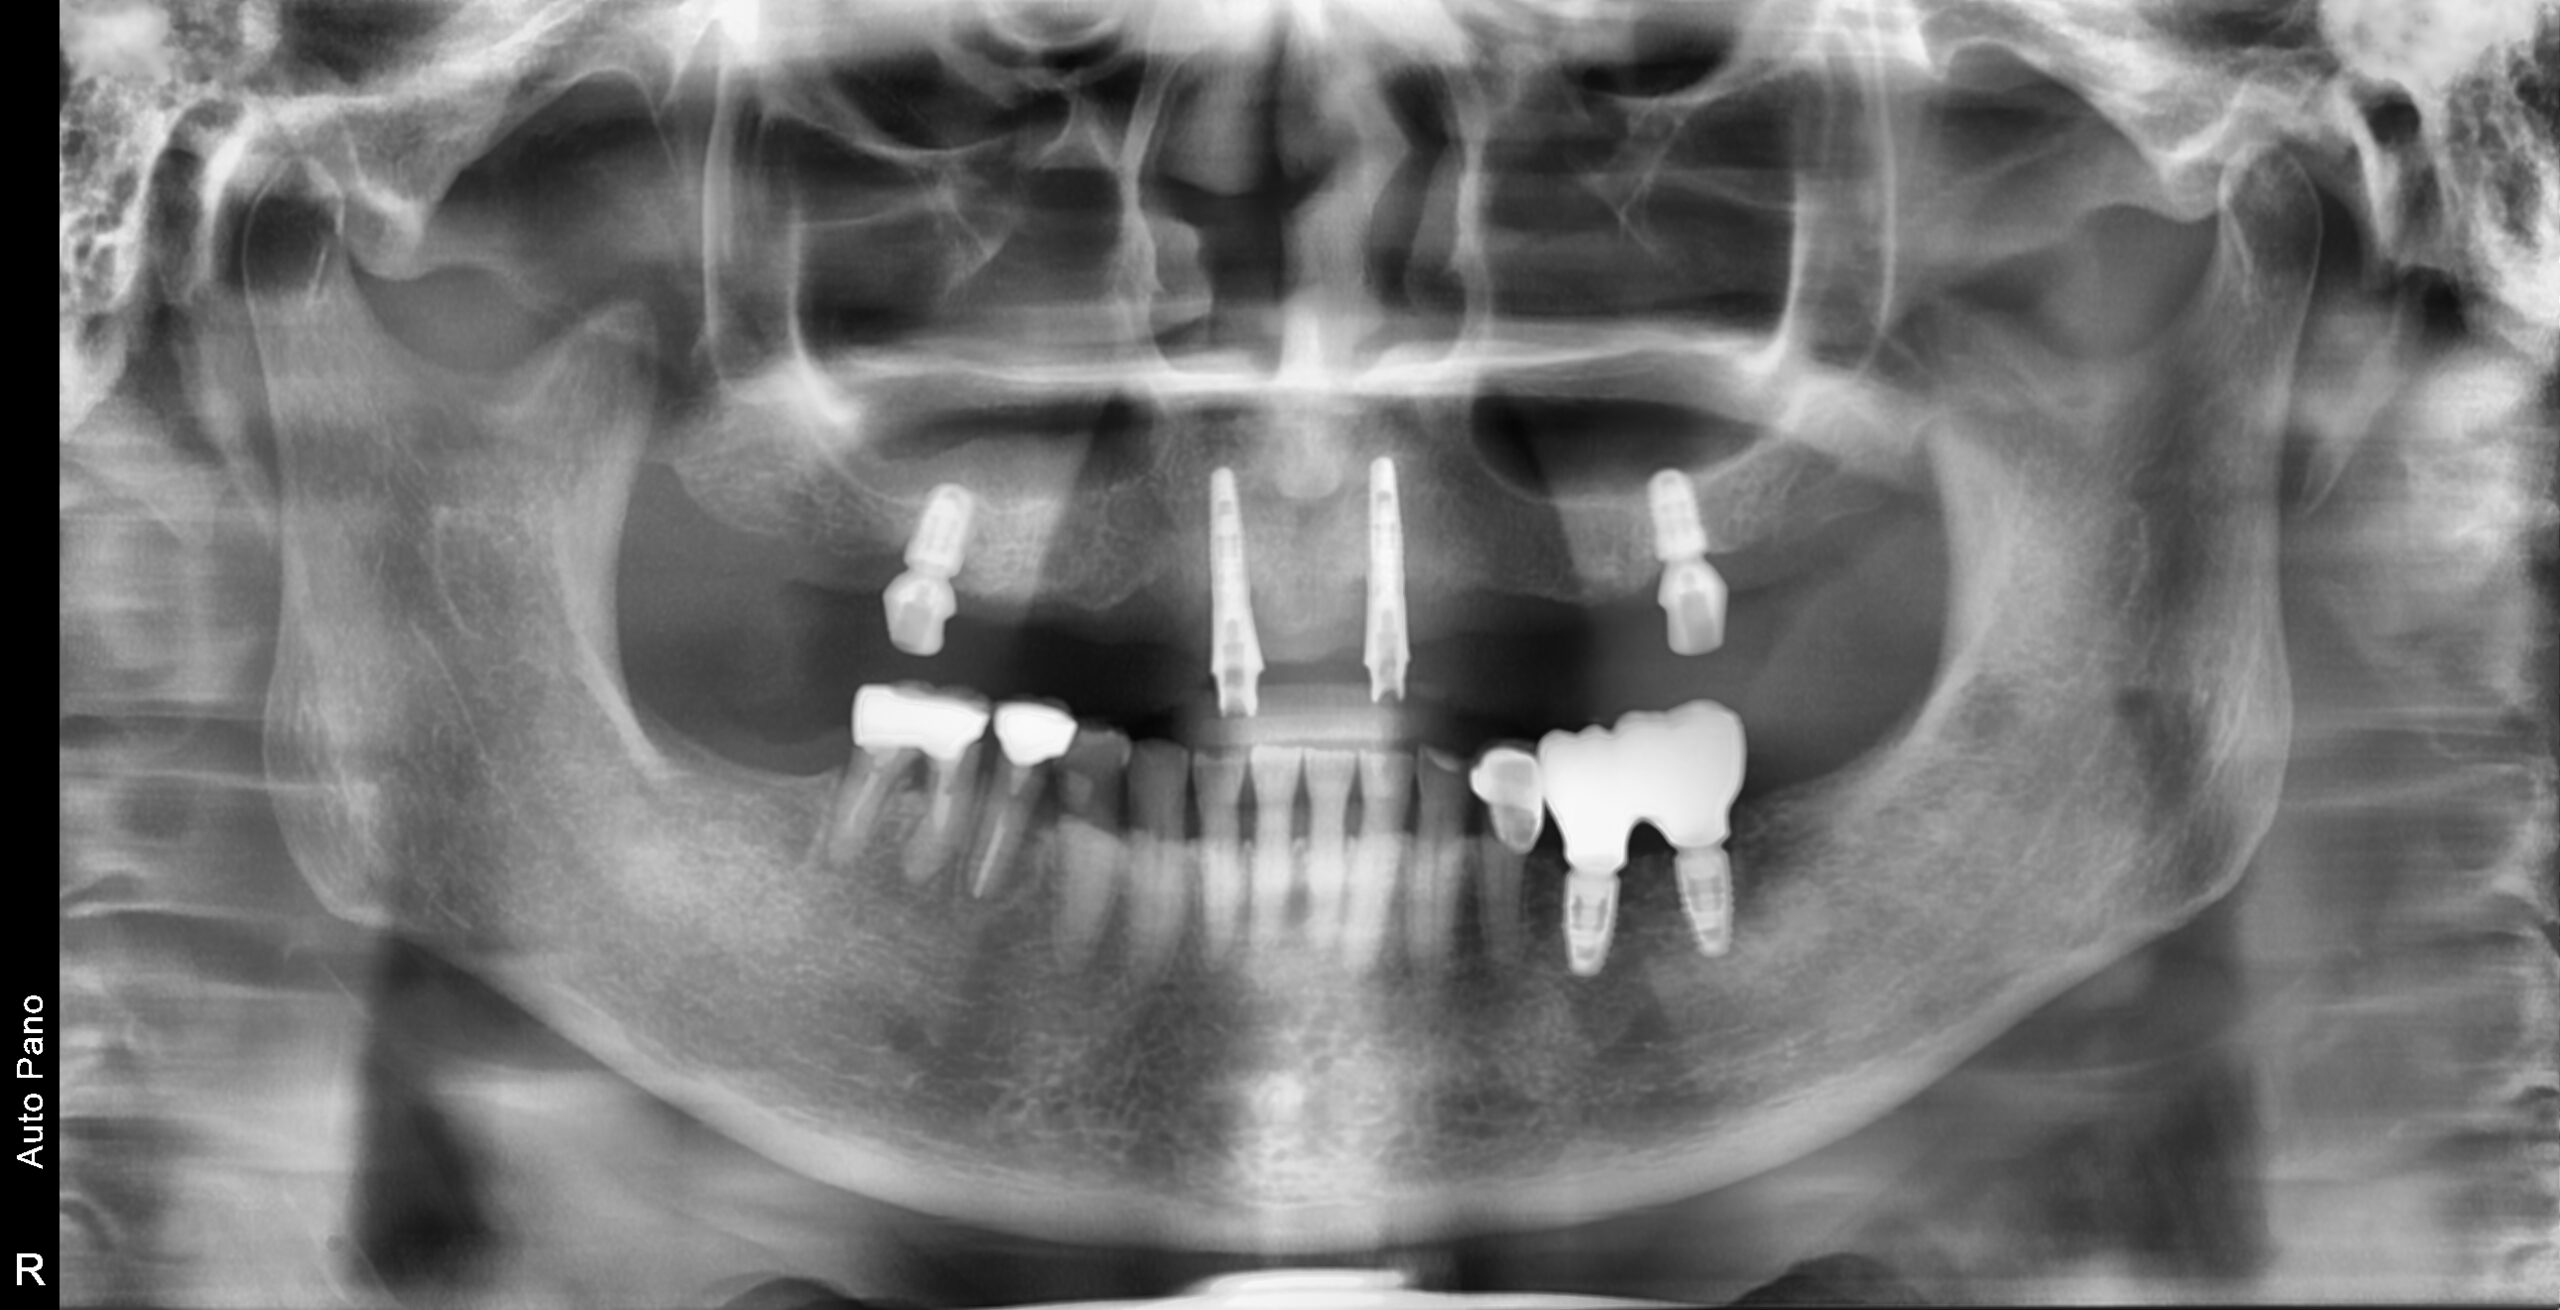

上顎は残っている歯の本数が少なく、部分入れ歯が破損している状態で、日常生活に支障が出ている状態でした。

・上顎:3・3・4・6番のみ残存

・下顎:左下の奥歯のみ欠損

▼上顎

実際には抜歯が必須ではない歯もありましたが、噛み合わせの平面を整えたうえで総義歯を管理しやすくするため、相談のうえで抜歯を選択。

その後、上顎に4本のインプラントを埋入しました。

▼下顎

過去にブリッジ治療が行われていた部分を撤去し、インプラント治療へ変更。

骨が不足していたため、骨移植(GBR)を併用しています。